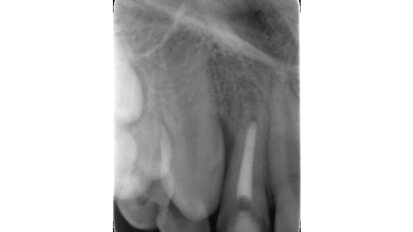

Hybridní terapie alignery